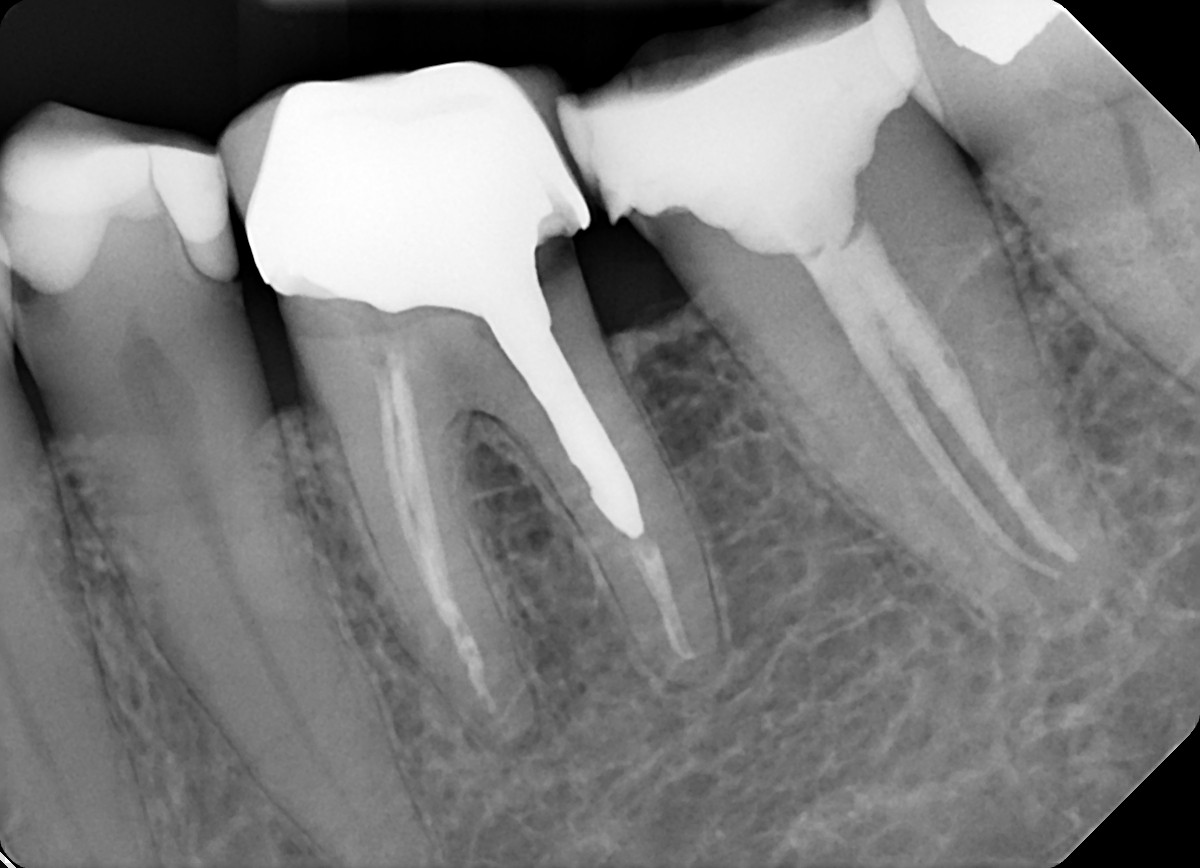

4. Evaluate the root canal treatment of tooth # 3.6?